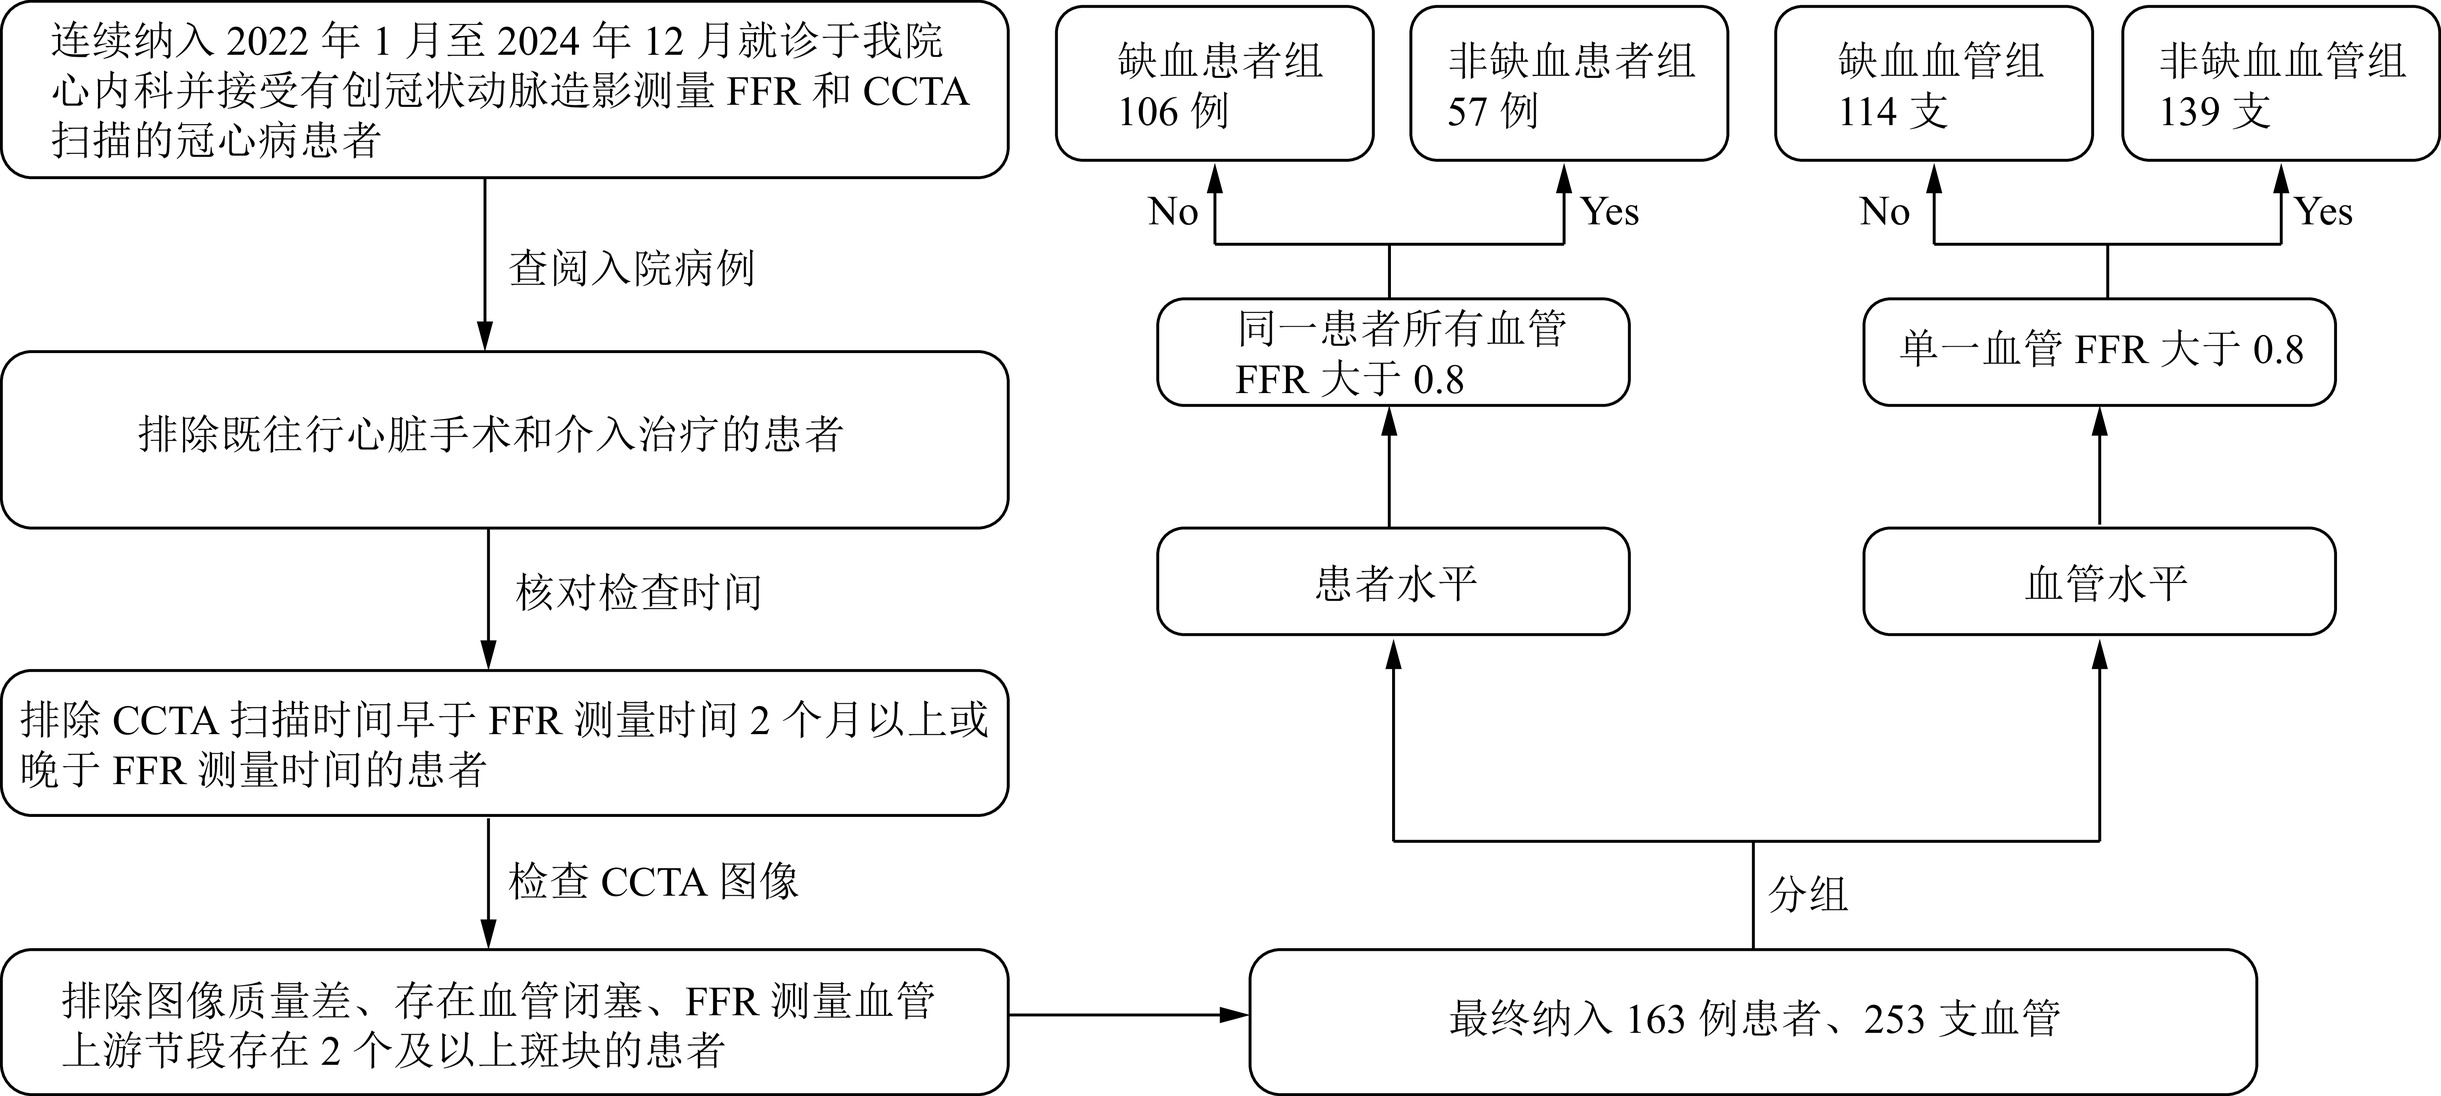

目的:比较缺血组与非缺血组的CCTA斑块特征差异,探求对诊断心肌缺血有价值的斑块特征定性及定量指标,在临床工作中应用,尽早发现可能存在心肌缺血的受检者。方法:连续纳入2022年1月至2024年12月就诊于我院心内科并接受有创冠状动脉造影测量FFR和CCTA扫描的冠心病患者进行回顾性分析。以患者水平分组分析一般资料。以血管水平分组分析CCTA斑块特征信息。斑块分析由两名具有5年以上CCTA诊断经验的放射科医师在未知分组的情况下使用半自动斑块分析软件进行。结果:研究共纳入163例患者,缺血患者组与非缺血患者组的一般资料无统计学显著差异。本研究共纳入253支血管,缺血血管组纳入114支血管,非缺血血管组纳入139支血管。斑块特征定性指标中,缺血血管组的餐巾环征、点状钙化比例高于非缺血血管组,两组的正性重构、低密度斑块指标无统计学显著差异。斑块定量指标中,两组的PL、PB、MLA、MDS、MAS、RI具有统计学显著差异,PV、EI无统计学显著差异。PL、PB、MLA、MDS、MAS、RI诊断斑块所属血管供血区域的心肌缺血的AUC分别为0.672、0.712、0.843、0.830、0.821、0.655,联合检测的AUC为0.844,高于单一指标诊断。结论:CCTA斑块特征分析在预测心肌缺血中具有很大潜力,多种斑块特征定量指标联合诊断对预测心肌缺血具有更高的效能。

Abstract:Objective: To compare the differences in coronary computed tomography angiography (CCTA) plaque characteristics between ischemic and non-ischemic groups and to explore qualitative and quantitative plaque features that are valuable for diagnosing myocardial ischemia. This study aimed to apply these indicators in clinical practice to identify patients with potential myocardial ischemia as early as possible. Methods: A retrospective analysis was conducted on patients with coronary heart disease who underwent invasive coronary angiography for fractional flow reserve (FFR) measurement and CCTA scanning in the cardiology department of our hospital between January 2022 and December 2024. General information was analyzed at the patient level, whereas CCTA plaque characteristics were analyzed at the vessel level. Plaque analysis was performed by two radiologists with more than five years of experience in CCTA diagnosis using semi-automatic plaque analysis software blinded to the patient groups. Results: A total of 163 patients were included in the study, with no statistically significant differences in general information between the ischemic and non-ischemic groups. A total of 253 vessels were included, with 114 vessels in the ischemic and 139 in the nonischemic vessel groups. Among the qualitative plaque characteristics, the napkin-ring sign and punctate calcification were more prevalent in the ischemic than in the nonischemic vessel group. No statistically significant differences were observed in positive remodeling and low-density plaque indicators between the two groups. Among the quantitative plaque characteristics, statistically significant differences in plaque length (PL), plaque burden (PB), minimum lumen area (MLA), minimum diameter stenosis (MDS), maximum area stenosis (MAS), and remodeling index (RI) were observed between the two groups. There were no statistically significant differences in plaque volume (PV) or edge irregularity (EI). The areas under the curve (AUCs) for diagnosing myocardial ischemia in the vascular supply areas of the plaques using PL, PB, MLA, MDS, MAS, and RI were 0.672, 0.712, 0.843, 0.830, 0.821, and 0.655, respectively. The AUC for the combined detection was 0.844, which was higher than that for any single indicator. Conclusion: CCTA plaque characteristic analysis has great potential for predicting myocardial ischemia, and the combined use of multiple quantitative plaque indicators provides higher diagnostic efficacy.